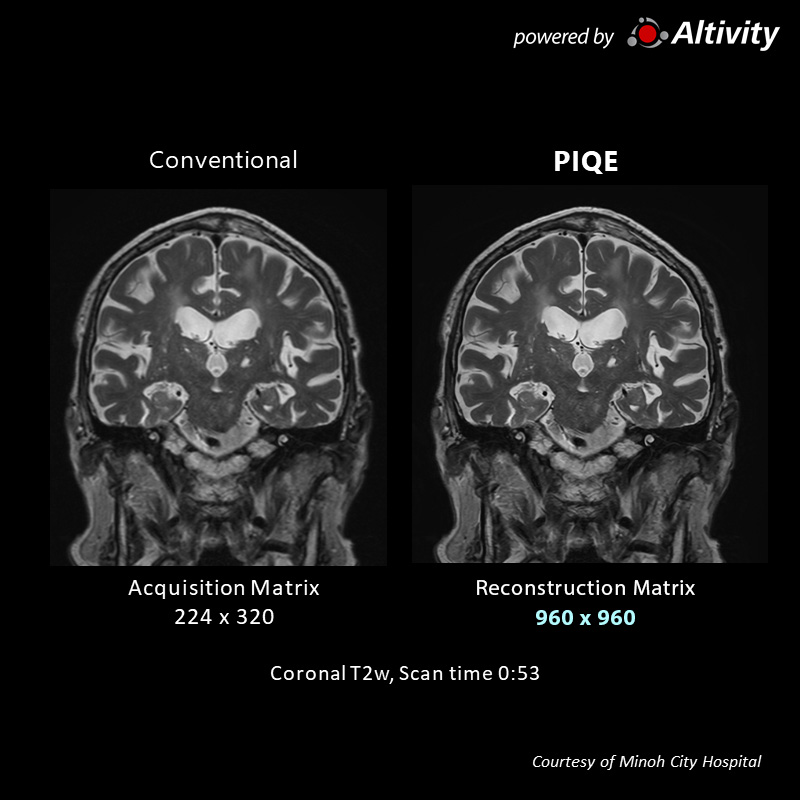

Sag T2w for pituitary

Using a regular head and neck coil, with a collection matrix 256 × 256 setting, imaging can be performed in approximately 1 minute. Structures around the pituitary gland are clearly visible.

Acquisition time: 1:08